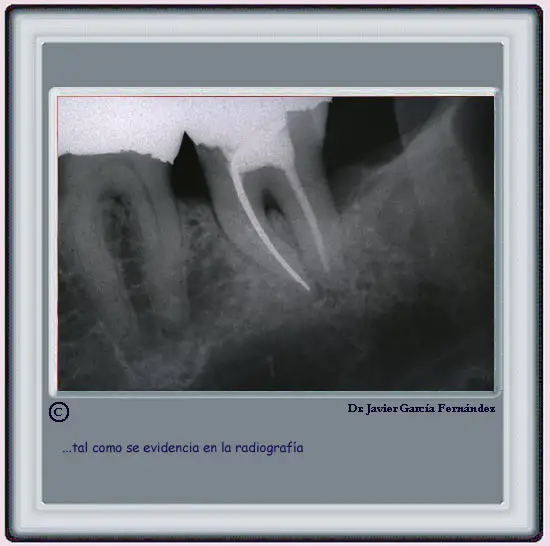

image157